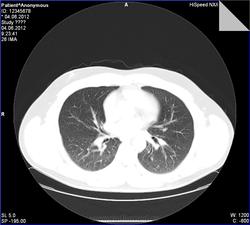

- https://radiomed.ru/sites/default/files/styles/case_slider_image/public/user/7898/0010.jpg?itok=6cAwCZeq

сделать снимок на выдохе для исключения обструкции

Обогащение рисунка, снижение пневматизации. сказать что -то конкретное -трудно. Сосудистое окно бы посмотреть. На выдохе- да было бы неплохо.

Ой, прошу прощения! Я тормоз! Там же 3 серии: 1 - топограмма, вторая на вдохе, а третья - на выдохе)))) Сергей Николаевич, Ваши иллюстрации с серии на выдохе.Радостно посмотрела на вдохе - чисто!

Пример скана на одном уровне при фазах дыхания).

По экспираторной КТ - норма, "ловушек" нет, значит и обструкции нет, что и требовалось доказать, что соответствует заключению по ФВД ( сам интерпретировать параметры не смогу полноценно, со времен учебы подзабыл, а во время работы вникать в цифры не приходилось). Может, кто разбирается и прокомментирует.

Предоставленные в первом посте томограммы - экспираторная КТ, можно не только на слово

Томография: рентгенологически патологии не визуализировано